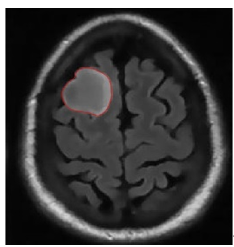

5.4 Results on brain MRI images

To achieve accurate segmentation of medical images, we have carefully tuned the parameters α, λ, and μ, which play a critical role in the performance of the DRLSE algorithm. These parameters control key aspects of the level set evolution, such as the smoothness of the contour (α), the fitting to the object boundaries (λ), and the regularization of the level set function (μ).

Using an empirical approach, we iteratively adjusted these values to obtain the best segmentation results for the images shown in Figure 10. Specifically, for brain MRIs, we found that setting α=0.5, λ=6, and μ=0.02 provided optimal segmentation results. These values effectively balance the trade-off between contour smoothness and accuracy in detecting object boundaries.

The segmentation process required several iterations to refine these parameters, highlighting the importance of adapting them to the specific characteristics of the images being analyzed. The results confirm the robustness of the DRLSE algorithm in delimiting structures in medical images.

Figure 10. Segmentation result. with the DRLSE algorithm